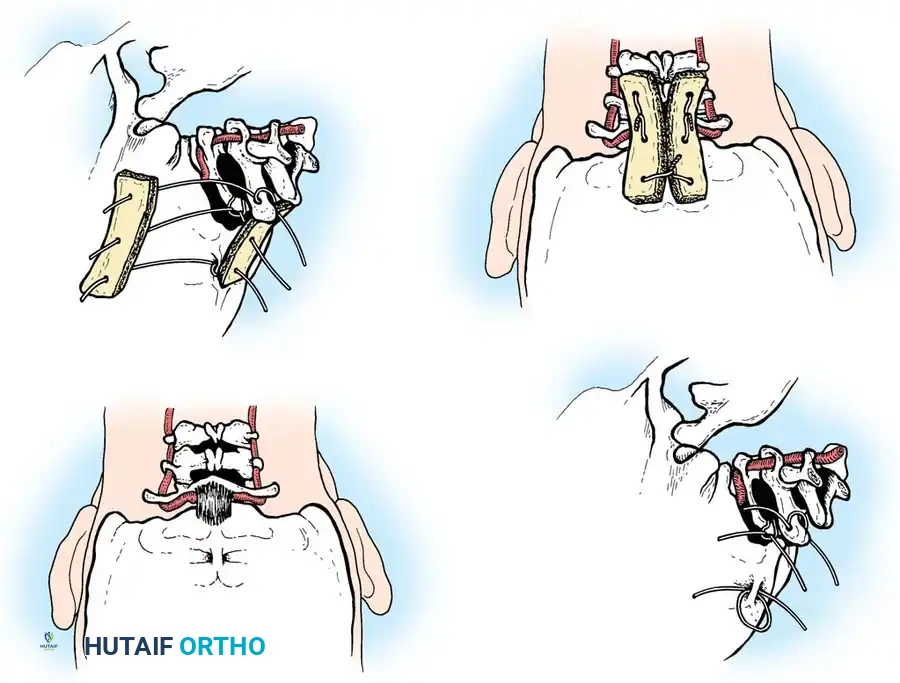

Posterior Cervical Fusion (PCF) and Instrumentation

Indications: Posterior tension band failure, irreducible facet dislocations requiring open reduction, or multi-level instability.

Positioning & Approach:

* The patient is carefully log-rolled prone onto a Jackson table. The head is secured in a Mayfield pin fixator.

* A midline posterior incision is made, utilizing the avascular ligamentum nuchae plane to expose the spinous processes, laminae, and lateral masses out to the medial border of the facet joints.

Surgical Steps:

1. Open Reduction: If a facet is dislocated, carefully lever the inferior articular process of the superior vertebra over the superior articular process of the inferior vertebra using a Penfield elevator.

3. Rod Contouring: Contour titanium or cobalt-chrome rods to match the patient's natural cervical lordosis and secure them to the screw heads with set screws.

4. Decortication and Fusion: Aggressively decorticate the lateral masses and facet joints with a high-speed burr. Pack the gutters with cancellous autograft (often harvested from the iliac crest) or high-quality allograft.

Fig 7. Posterior cervical lateral mass screw and rod construct, providing excellent biomechanical stability for posterior tension band failures.